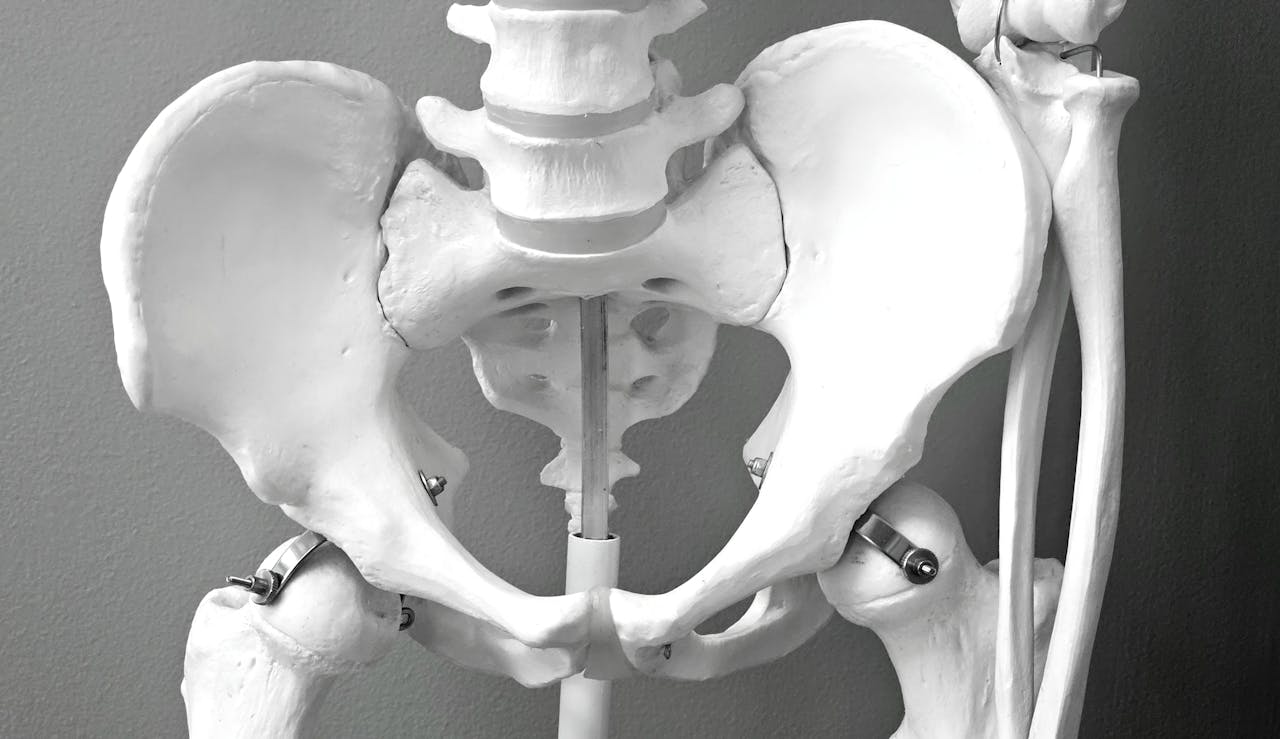

Choroba zwyrodnieniowa stawu biodrowego (koksartroza) to postępujące zwyrodnienie stawu, które w rezultacie stopniowego niszczenia chrząstki stawowej prowadzi do ograniczenia funkcji stawu biodrowego i poważnych dolegliwości bólowych. Niezależnie od tego, czy jest to zwyrodnienie stawu wynikające z wieku, urazów, czy czynników genetycznych – efekt końcowy jest ten sam: osłabienie ruchomości stawu, ograniczenie ruchomości biodra i znaczne utrudnienie codziennego funkcjonowania.

Podstawą diagnostyki jest badanie fizykalne – ocena zakresu ruchomości stawu, siły mięśniowej w obrębie stawu biodrowego, metoda Trendelenburga (stabilność), testy prowokujące konflikt udowo‑panewkowy. Lekarz ocenia także różnice długości kończyn oraz wzorce chodu.

- RTG (rentgen) stawu biodrowego – podstawowe badanie oceniające postęp zwyrodnienia: zmniejszenie przestrzeni między panewką a głową kości udowej, osteofity, deformacje głowy kości udowej, sklerotyzacja.

Implant składa się z panewki, głowicy (kuli) i trzpienia mocowanego do głowy kości udowej. W zależności od przypadku stosuje się: